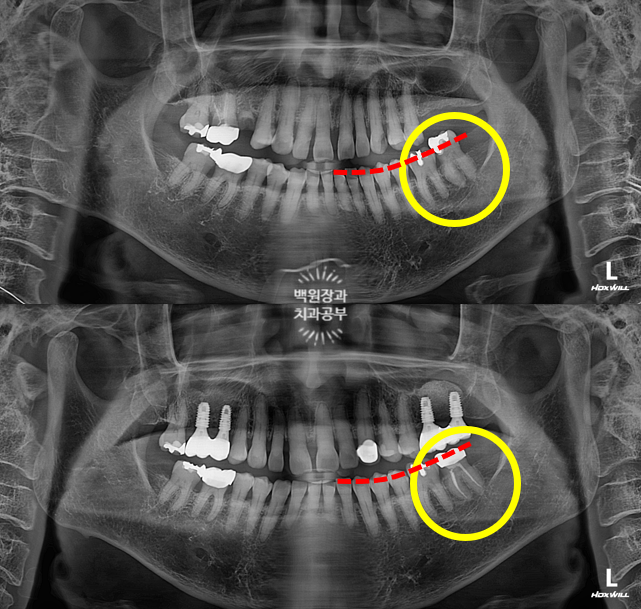

보철물 완성 후 촬영한 치과용 파노라마 사진입니다.

보시면 부분 교정 치료 후 오른쪽 위 두번째 큰어금니는 함입되어 제 자리로 돌아갈 수 있었고,

덕분에 추가로 삭제할 필요 없이, 아래 임플란트를 온전하게 제작할 수 있었어요.

Before & After!!

뿌리만 남은 오른쪽 아래 두번째 큰어금니와 오른쪽 위아래 사랑니를 발치했고,

약 5개월의 부분교정을 통해 내려와있던 오른쪽 위 두번째 큰어금니를 제자리로 올려주었습니다.

그리고 스트라우만 임플란트로 오른쪽 아래 두번째 큰어금니의 기능을 회복시켜주었어요.